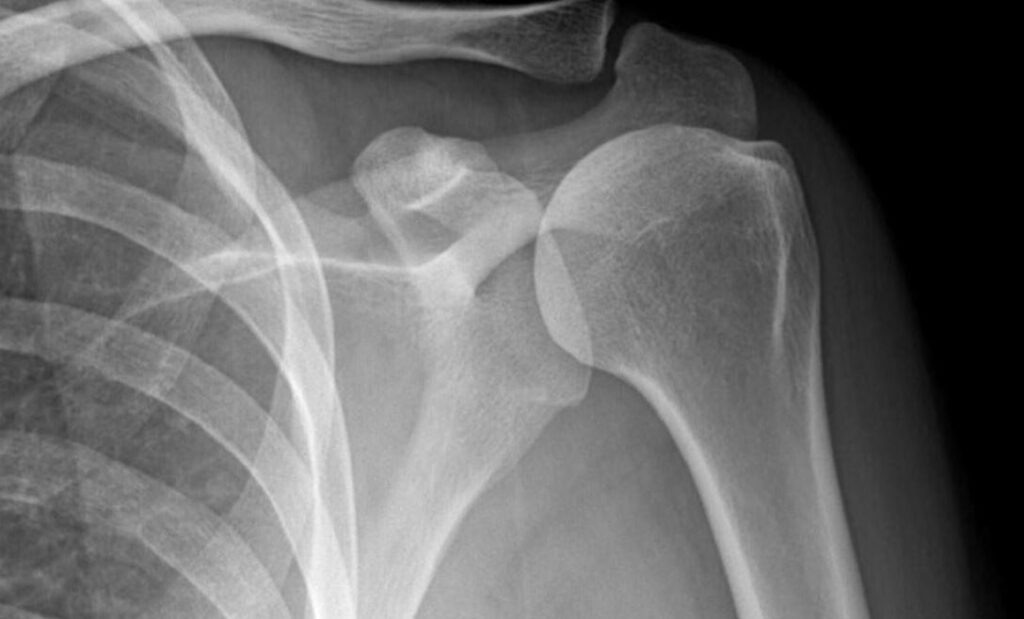

- Chụp X-quang khớp vai: Hiển thị những hình ảnh về bất thường trong cấu trúc xương ở vùng mỏm cùng của vai, hay các vùng bị vôi hóa gân cơ xung quanh khớp vai.